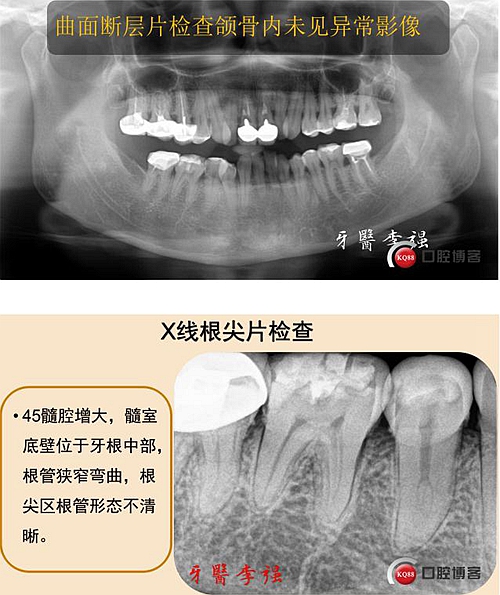

第二前磨牙重度牛牙癥伴C型根管病例 科貿(mào)嘉友收錄